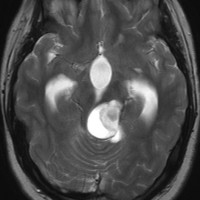

左はT1強調画像,右はFLAIR画像です。中脳視蓋が腫れて腫瘍がにじむように広がっているのがわかります。この腫瘍本体は15歳の時から21歳の時まで大きくなっていないので,中脳視蓋グリオーマ tectal gliomaの診断です。

T1強調ガドリニウム増強画像です。15歳の時は腫瘍の半分以上が強くガドリニウム増強されていましたが,この21歳の時の画像では,中心部やや右寄りに増強像が認められるだけです。この性質は,腫瘍が毛様細胞性星細胞腫であることを示しています。

左はT2強調画像,右はFLAIR画像です。中脳視蓋 tectum の中でも上丘が腫瘍化していることが解りますし,松果体は正常の大きさで腫瘍の上に乗っていますから,松果体腫瘍ではないことが解ります。上髄帆にも浸潤しています。